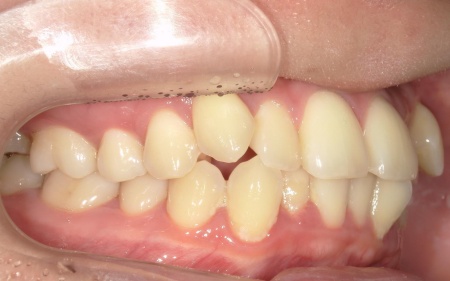

20代女性 八重歯と歯並びの乱れをマウスピース矯正装置で改善した症例

拝見したところ、歯が正しく並ぶためのスペースが不足しており、歯が重なって生えてしまう叢生(そうせい)の状態が全体的に見られました。

特に上下の糸切り歯が外側にずれている、いわゆる八重歯が目立っています。

患者様の場合は上下あごの位置関係から噛み合わせに大きな問題はなく、横顔のバランスや鼻先とあごを結んだEラインにも目立った乱れは見られませんでした。

そのため、歯の位置や傾きを整えることで歯並びを改善できると診断しました。